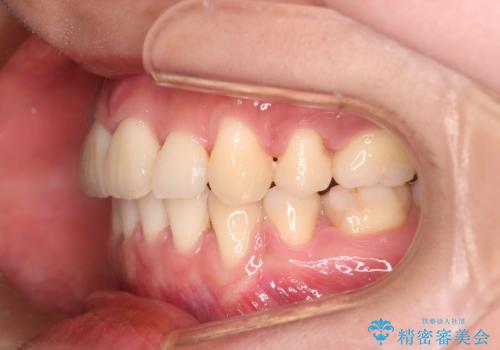

主訴である前歯のデコボコが改善され、噛みあわせも綺麗になりました。

歯肉退縮もなく、予定通りに治療を終えることができ良かったです。